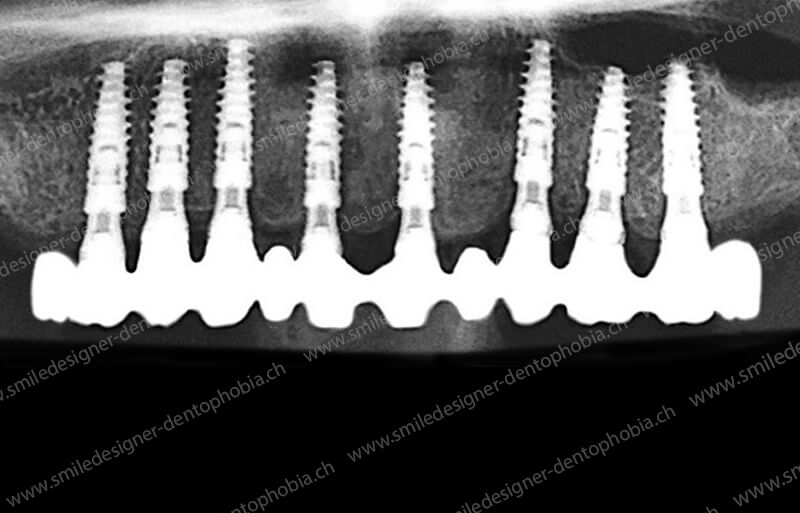

Cas clinique « GOLD DAMAGE CONTROL MCI » maxillaire : Bridge implanto-porté avec extensions postérieures (ALL ON 8). Version définitive des bridges avec un cosmétique en céramique.